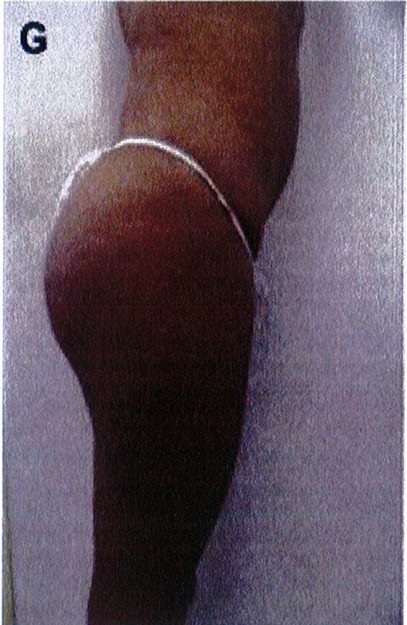

Hình. 3. (A-H) Tiền phẫu, chu phẫu và sau hậu phẫu 6 tháng của một bệnh nhân nữ 38 tuổi đươc ghép túi đôn mông với thể tích 330 cm3.

Hình. 4. (A-I) Hình ảnh tiền phẫu, chu phẫu và sau hậu phẫu 11 tháng của một phụ nữ 25 tuổi đã được thực hiện hút mỡ vùng éo, hông và sau xương vùng, đồng thời ghép khối cấy thể tích 270cm3.